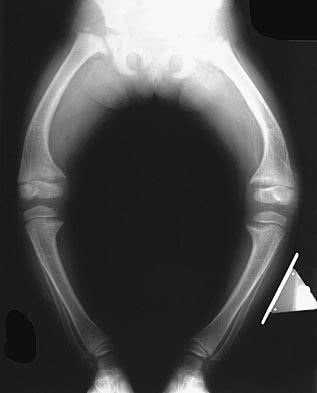

- Искривление нижних конечностей в о-образной форме.

Клинические исследования объясняют основной симптом болезни в том, что у человека появляются проблемы с развитием опорно-двигательного аппарата и происходят деформации нижних конечностей. Также у людей, больных фосфат-диабетом низкий рост, прослеживаются аномалии и других структур скелета, изменяется походка, могут прослеживаться боли при передвижении.

- 2 тип является аутосомно-доминантным, который не сцеплен с Х-хромосомой. Появляется на первом или втором году жизни. Проявляется в виде искривления нижних конечностей, изменениях скелета. При этом не изменяется процесс роста, человек имеет достаточно крепкое телосложение. Имеются легкие симптомы рахита.

С помощью инструментальной диагностики на предмет определения заболевания, происходит исследование метафиза, который при фосфат-диабете становится шире. Также показатели могут казаться кортикального слоя, значительно утолщенного.